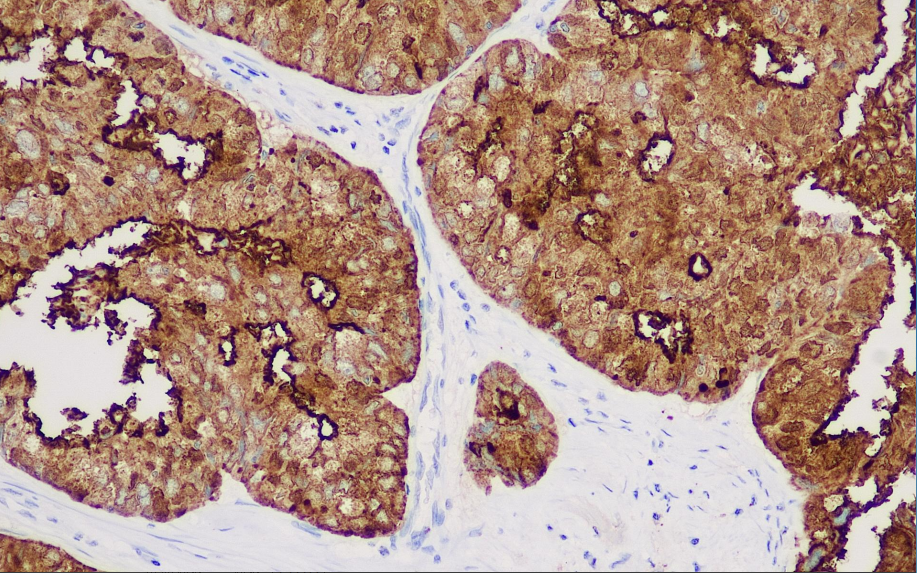

Positive control: Colorectal cancer

Mucins are a group of high molecular weight glycoproteins whose synthesis and secretion are among the characteristics of glandular epithelial tissue. Mucin 1 is expressed in many benign plasmacytoid tumors and is decreased in benign mucinous tumors; in malignant tumors, it is usually expressed in adenocarcinomas and at the junction of plasmacytoid and mucinous tumors. Its concurrent expression with Muc-2 correlates with the malignancy of ovarian mucinous tumors.

The MUC-1 antibody reagent can specifically bind to the MUC-1 molecule antigen. The immunohistochemical kit containing the MUC-1 antibody reagent is suitable for the precise diagnosis of adenocarcinoma (such as breast cancer, pancreatic cancer, and ovarian cancer).